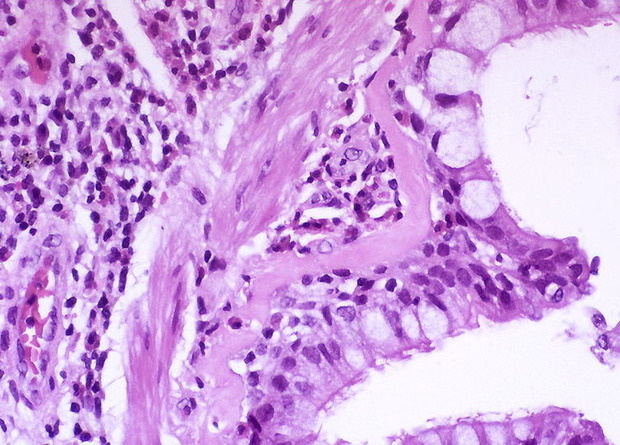

При контакте с аллергеном в дыхательных путях больного астмой продуцируются иммуноглобулин IgE и интерлейкины 4 и 13 (IL-4 и IL-13). Это приводит к каскаду реакций, характеризующихся продукцией слизи и повышенным содержанием эозинофилов в тканях. Антитела, блокирующие